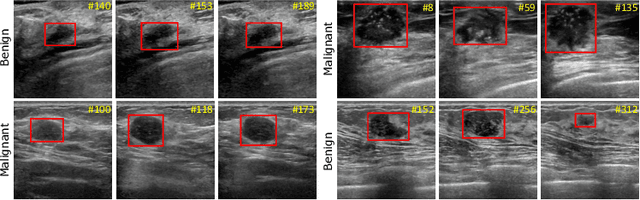

Breast lesion detection in ultrasound is critical for breast cancer diagnosis. Existing methods mainly rely on individual 2D ultrasound images or combine unlabeled video and labeled 2D images to train models for breast lesion detection. In this paper, we first collect and annotate an ultrasound video dataset (188 videos) for breast lesion detection. Moreover, we propose a clip-level and video-level feature aggregated network (CVA-Net) for addressing breast lesion detection in ultrasound videos by aggregating video-level lesion classification features and clip-level temporal features. The clip-level temporal features encode local temporal information of ordered video frames and global temporal information of shuffled video frames. In our CVA-Net, an inter-video fusion module is devised to fuse local features from original video frames and global features from shuffled video frames, and an intra-video fusion module is devised to learn the temporal information among adjacent video frames. Moreover, we learn video-level features to classify the breast lesions of the original video as benign or malignant lesions to further enhance the final breast lesion detection performance in ultrasound videos. Experimental results on our annotated dataset demonstrate that our CVA-Net clearly outperforms state-of-the-art methods. The corresponding code and dataset are publicly available at \url{https://github.com/jhl-Det/CVA-Net}.